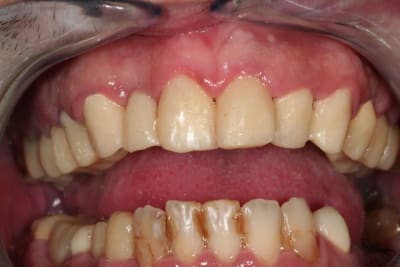

salut les petits clous...

voilà, je me suis remis un peu au boulot.

voici quelques images....

juste une remarque: pour l'instant je suis à la même DV.

non catrose, pas d'ortho.

on va un peu tricher avec la prothèse.